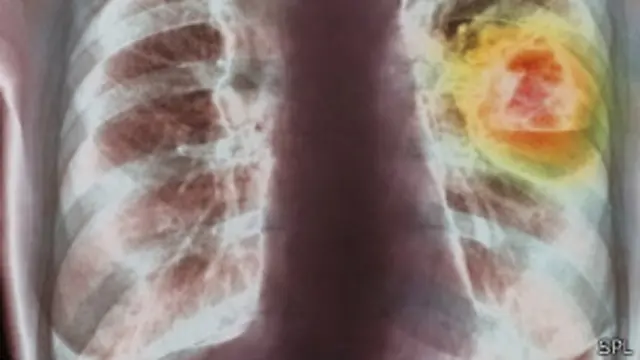

Dari 14 juta penderita kanker di seluruh dunia, 1,8 juta di antaranya (atau sekitar 13%) adalah kanker paru-paru yang biasanya disebabkan oleh kebiasaan merokok.